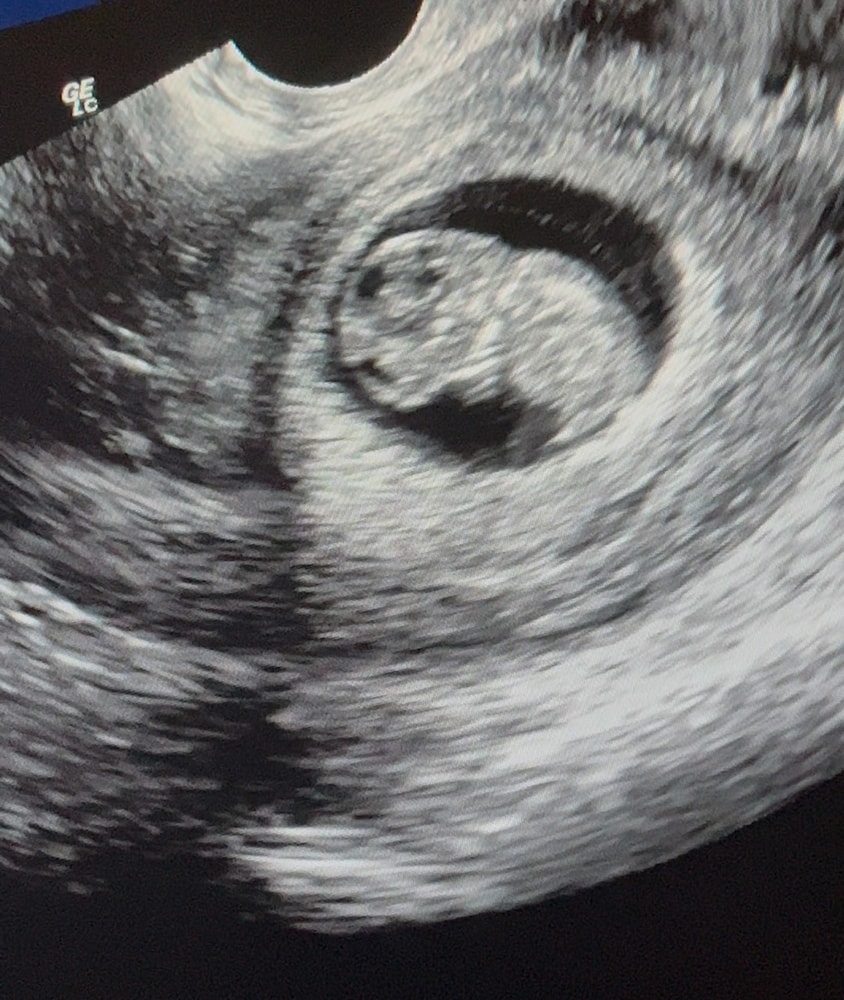

9 недель

Обследования, узи, анализыСегодня прибежала на узи, врач спросила чего так рано, ничего ж ещё не поменялось, но картинка получилась совсем другая 😁 эмбрион догнал акушерский срок и сравнялся, на данный момент 9 нед. КТР 24

Я наконец увидела шевеления 🥲😍